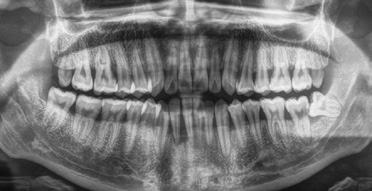

Zur Verdeutlichung sollen die neuen Kriterien abschließend auf einen konkreten klinischen Fall angewendet werden (Abb. 1–3). Es handelt sich um einen 25-jährigen Patienten, der sich auf Überweisung des Hauszahnarztes vorstellt und über zunehmende Schmerzen beim Abbeißen und eine seit Tagen bestehende und größer werdende Gingivaschwellung im Frontzahnbereich des Unterkiefers berichtet. Die allgemeinmedizinische Anamnese ist unauffällig, der Patient ist Nichtraucher. Intraoral zeigt sich eine druckdolente Schwellung vestibulär in regio 41/42, massive Zahnsteinablagerungen lingual an den unteren Frontzähnen und vestibulär der oberen Molaren, Entleerung von Pus aus den Sulci der Zähne 31 – 43. Einzelne Zähne weisen eine pathologische Mobilität auf (42/Grad III, 41/II, 31/I, 32/I) bei positivem Befund der thermischen Vitalitätsprüfung.

Aus den klinischen und röntgenologischen Befunden können als Diagnosen formuliert werden:

- parodontaler Abszess in regio 42 und 41 als Folge einer bisher unbehandelten Parodontitis

- Parodontitis (Stadium III, generalisiert; Grad C – schnelle Progression)

Das Staging folgt aus den klinischen und röntgenologischen Parametern, da mehrere Zähne Sondierungstiefen über 6 mm und einen vertikalen Knochenabbau aufweisen (Abb. 2 und 3; vgl. Tab. 2). Zum Grading existiert zwar keine direkte Evidenz für einen Attachmentverlust von mehr als 2 mm in den vergangenen 5 Jahren, da keine Befunde aus der Vergangenheit vorliegen. Der Quotient aus prozentualem Knochenverlust und Alter erreicht aber an mehreren Zähnen einen Wert von über 1,0. Trotz der hohen Menge an vorhandenem Biofilm übersteigt die schon stattgefundene parodontale Destruktion erheblich das für einen 25-jährigen Patienten erwartbare Ausmaß. Der Patient stellt sich zudem in einem Stadium rascher Krankheitsprogression vor (vgl. Tab. 3).

Auf der Grundlage dieser Diagnosen können die Behandlungsplanung und die prognostische Einschätzung erfolgen. Der parodontale Abszess erfordert eine Akutbehandlung vor Beginn der systematischen Parodontitistherapie. Eine Erkrankung im Stadium III (schwere Parodontitis) bedingt über die mechanische antiinfektiöse Therapie hinaus komplexe, ggf. chirurgische parodontologische Interventionen. Die vermutete schnelle Progression (Grad C) gibt Hinweise auf mögliche Probleme während der Therapie und auf ein erhöhtes Risiko für Rezidive und weiteren Attachmentverlust in der Zukunft. Diese Faktoren müssen in der Patientenberatung und individualisierten Therapie zur Auswahl der Therapieoptionen mit der höchsten Evidenz für einen Behandlungserfolg und für die Organisation der Erhaltungstherapie berücksichtigt werden.